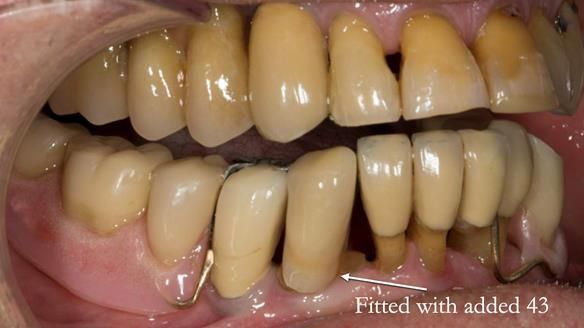

In 2022, tooth 43 fractured.

An artificial tooth was added to the RPD

by welding a cobalt–chrome tag to the bar

and adding the tooth.

The denture continued to function extremely well.

The way Rowan lengthened the teeth — particularly in the upper RPD — to match the existing gingival recession on the remaining teeth was superb. The dentures sit naturally within the context of the rest of the mouth.